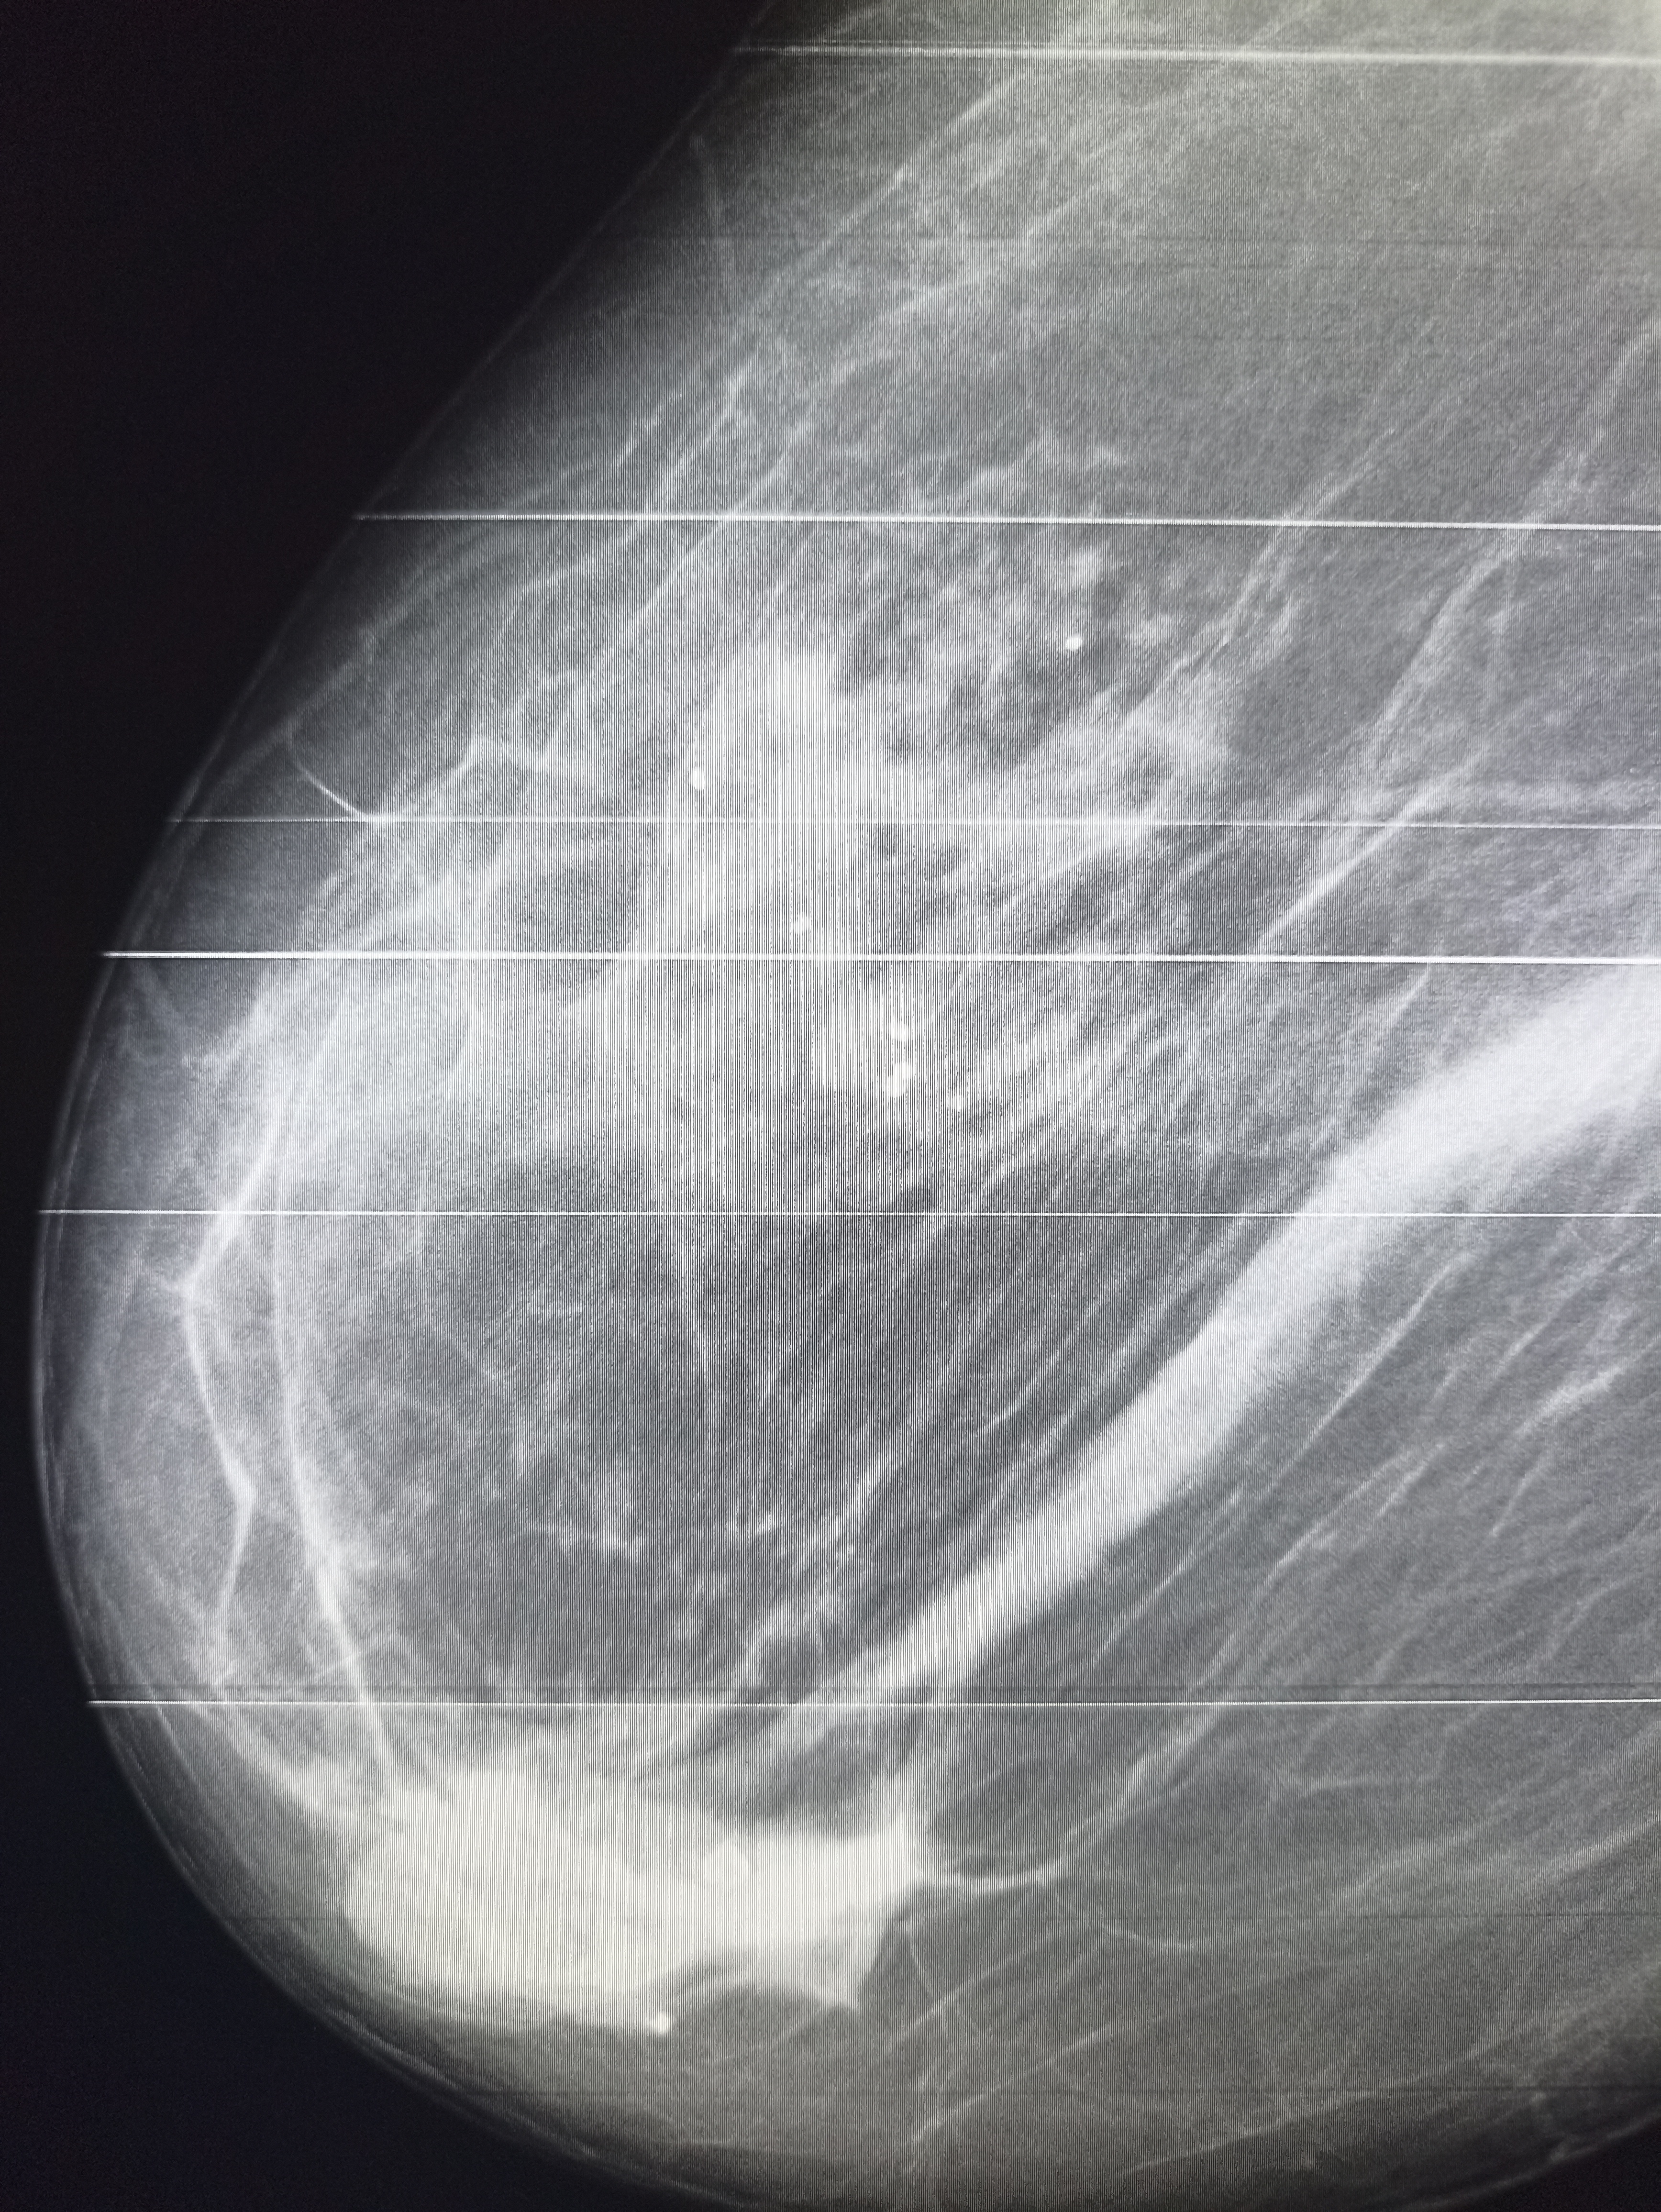

И снова здравствуйте! Сегодня! В этом тредике! Мы будем с вами общатся и играть в доктора! Я буду вам постировать фоточки, а вы угадывать пиздецомы! Я все еще нихуя не успеваю, пытаюсь описать за 25 число, сегодня задержусь наверное после работы опять пытаясь нагнать нагрузку :-(